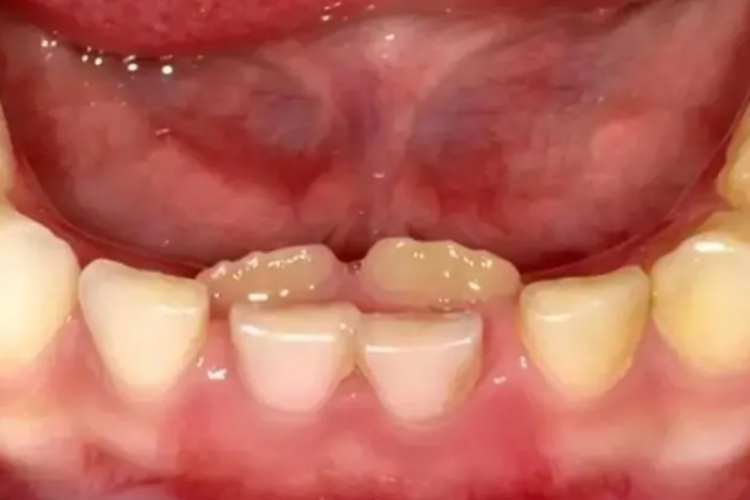

乳牙滞留是指继承恒牙萌出,未能按时脱落的乳牙,或恒牙未萌出,保留在恒牙列中的乳牙。混合牙列时期,最常见的是下颌乳中切牙滞留,后继之恒中切牙于舌侧萌出,乳牙滞留于唇侧,呈“双排牙”现象。

当恒牙异位萌出,乳牙尚未脱落,应及时拔除滞留的乳牙,解除恒牙萌出的障碍。当下颌切牙出现“双排牙”现象时,建议尽早拔除滞留的乳切牙,但不建议拔除其他邻近的乳牙。拔除其他邻近的乳牙只能暂时缓解拥挤,可能会导致更严重的牙弓长度不足。